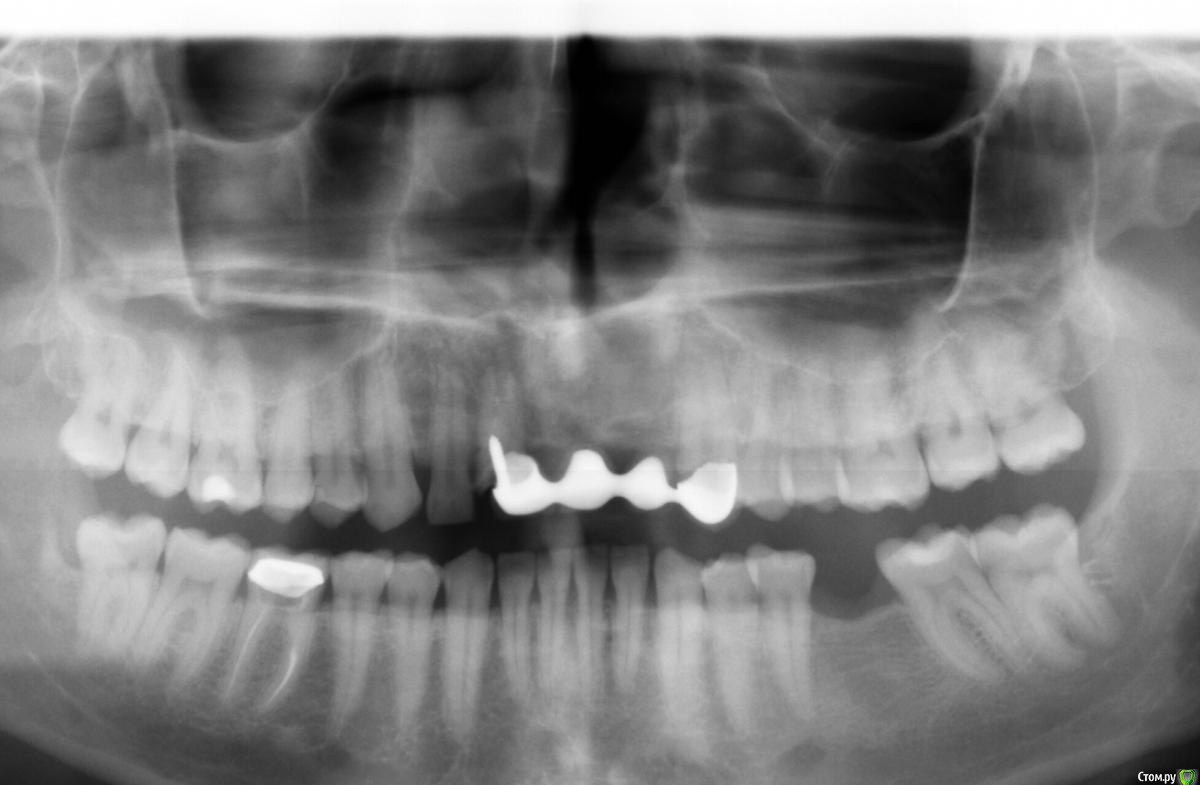

bearserg Опубликовано 20 октября, 2016 Поделиться Опубликовано 20 октября, 2016 Помогите принять решение.Прием у стоматолога уже в 16-00))Согласно плану лечения будет делаться наращивание альвеолярного отростка. Нужно определиться, ставить 3 импланта или будет достаточно 2х и мостовидная коронка на 3 единицы.Какой вариант предпочтительнее с точки зрения оптимальности, а не жесткой экономии. Спасибо! Ссылка на комментарий